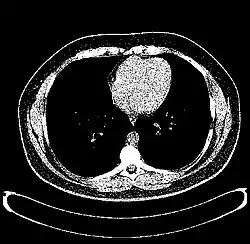

The Hounsfield scale (/ˈhaʊnzfiːld/ HOWNZ-feeld), named after Sir Godfrey Hounsfield, is a quantitative scale for describing radiodensity. It is frequently used in CT scans, where its value is also termed CT number.

A practical application of this is in evaluation of tumors, where, for example, an adrenal tumor with a radiodensity of less than 10 HU is rather fatty in composition and almost certainly a benign adrenal adenoma.[31]